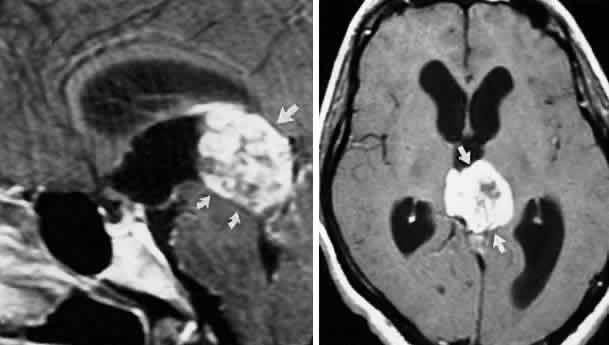

In the cavernous sinus, the abducens nerve may be involved in combination with the ophthalmic-trigeminal, third, or fourth nerves. Abducens monoparesis is frequent with cavernous sinus lesions, perhaps related to the nerve's location within the sinus, inferolateral to the carotid artery and unsupported by the dural wall of the sinus.19,20 Isolated abducens palsy occurs with carotid-cavernous fistulas (especially with spontaneous dural shunts21) and intracavernous aneurysms20 (Fig. 7), and is the earliest indication of contralateral spread of cavernous sinus thrombosis. Sixth nerve palsy accompanied only by ipsilateral Horner's syndrome also points to the cavernous sinus, since the ocular sympathetics from the carotid plexus may be simultaneously involved.22

Fig. 7. A. Chronic isolated sixth nerve palsy. B. Coronal and Axial (C) MRI sections showing large intracavernous internal carotid aneurysm (arrows).